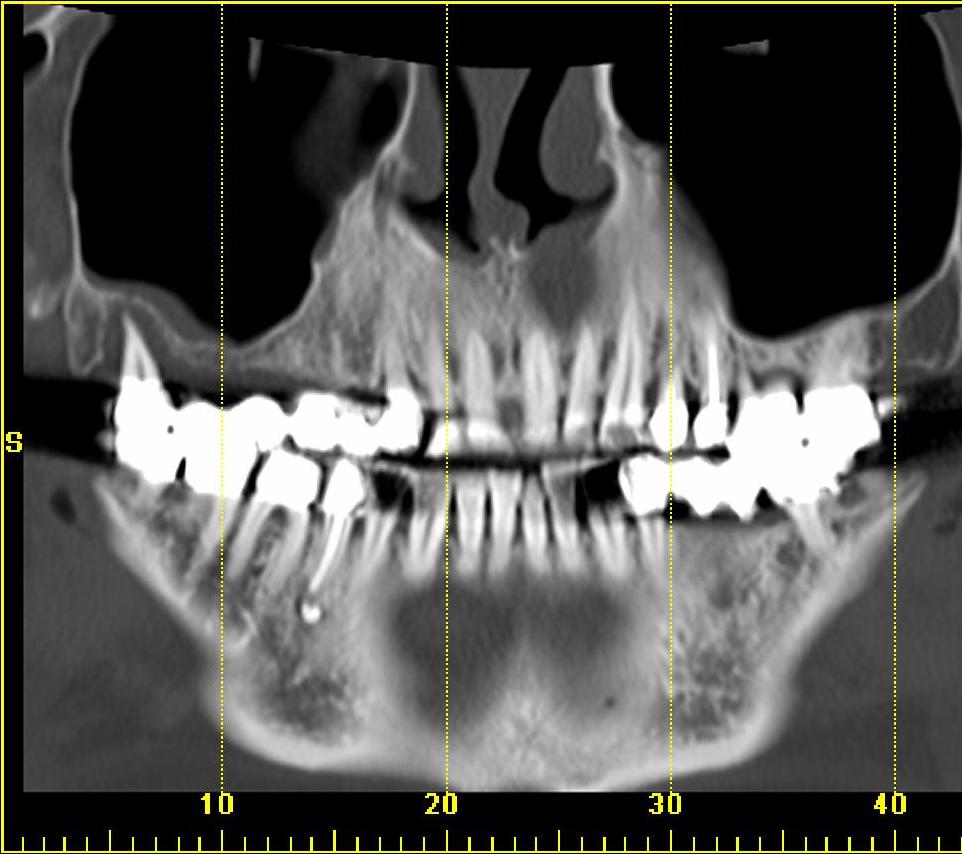

Die Dental-CT bietet im Vergleich zum konventionellen Orthopantomogramm (OPG) die Option der artefakt- und überlagerungsfreien Dentalrekonstruktion in jeglicher Ebene. Die Strahlenbelastung ist sicher höher als bei OPG und DVT, die diagnostische Wertigkeit ist jedoch auch höher. Das Röntgenverfahren reicht bei mangelnder Dreidimensionalität nicht für alle präoperative Fragestellungen, das DVT ist nur für knöcherne Hochkontrastbildgebung geeignet.

Indikationen zur Dental-CT sind dagegen alle Fragen im Bereich von Mund und Mittelgesicht wie Raumforderungen, Entzündungen, retinierte Zähne, angeborene Dysplasien, Diagnostik vor kieferchirurgischen Eingriffen, Zahnextraktionen oder Implantaten und Kontrollen nach therapeutischen Eingriffen. Für Kinder und Jugendliche besteht die Möglichkeit der Dosisreduktion.